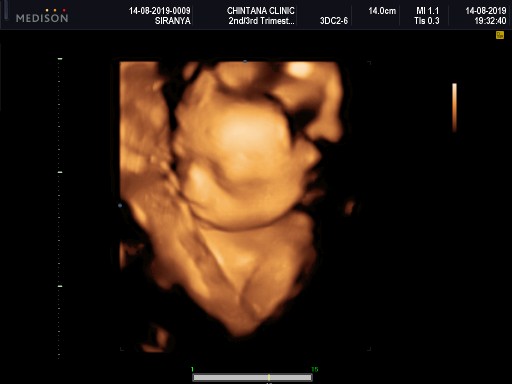

5เดือน

เเม่ท่านไหน5เดือนเห็นเเบบนี้ไหมค่ะ โชว์กันหน่อยค่ะเเม่ๆ

สาวน้อยตอน 21 วีคค่ะ ตอนนี้ 28 วีคแล้ว

ซาวตอน5เดือนกว่าจ้า. ได้ลูกชายค่ะ❤️

ตอน28วีคค่ะ ตอนนี้33วีคแล้วค่ะ

ชู 2 นิ้วใส่แม่เลยจ้า 26 วีค

บ้านนี้กว่าจะได้เห็น 25+5 ค่ะ

เพิ่งไปซาวมาวันนี้เลยค่ะ 20 w

สาวน้อย 31 วีคแล้วค่ะ